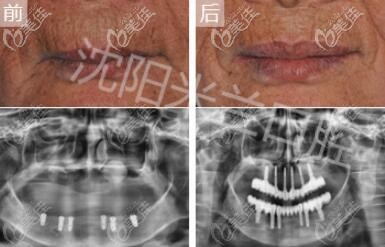

俗話說:種牙好不好,關鍵在于醫(yī)生,技術好的醫(yī)生可以事半功倍。今天來看下幾乎人人都稱贊的沈陽米蘭口腔李超醫(yī)生種植牙怎么樣,小編還收集了李醫(yī)生的種牙實例供參考。... b1621 G0 V0

牙齒缺失很多人都會選擇做種植牙,但是做種植牙選擇醫(yī)院很重要,而米蘭口腔作為沈陽地區(qū)一家大型連鎖口腔機構,已經(jīng)幫助很多牙友改善牙齒口腔問題,那么沈陽米蘭口腔做種植牙怎么樣?... b1174 G0 V0